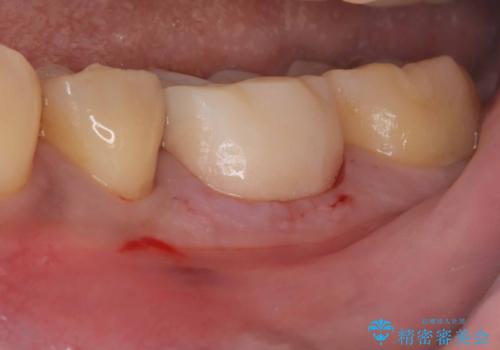

- 銀歯2本の下が虫歯になっていたので、フルジルコニアクラウンとセラミックインレーで治療を行いました。

適合が良い被せ物を入れるために、歯の境としっかり合わせた仮歯を入れ、歯茎の状態を良くしてからシリコンで型取りをしています。